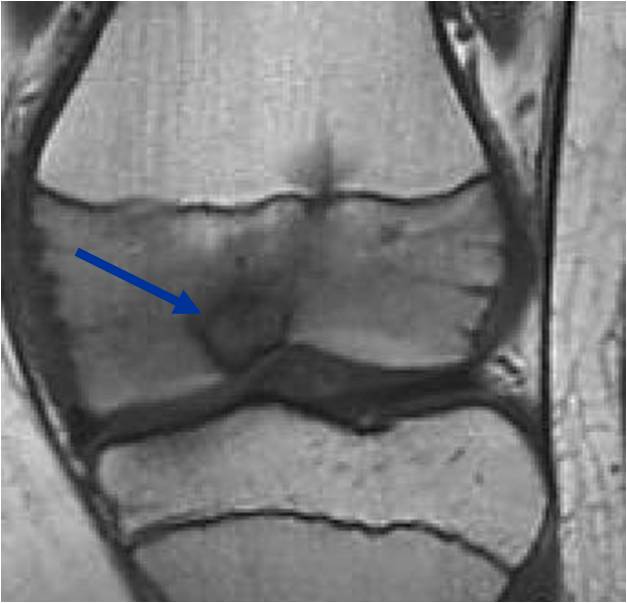

- (MRI appearance)

- Geographic, well circumscribed lesion in the epiphysis

- Intermediate Signal on T1

- High signal on T2 mixed with low signal areas (low signal areas proposed to be secondary to lysosomal content of highly cellular areas)

- Fluid/Fluid levels demonstrated in tumors that have undergone ABC change (aneurysmal bone cyst change)

- Extensive Surrounding edema is common

- Joint effusion in 30-50% of cases